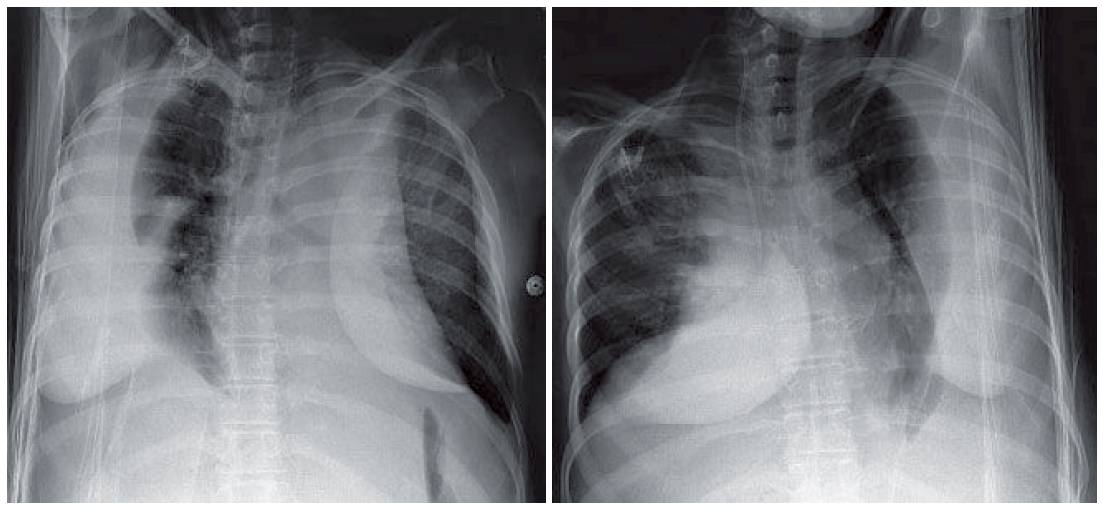

- Frontal radiograph (Fig. 1) shows increased distance between the stomach bubble and the left aerated lower lung. The right diaphragmatic peak is displaced lateral to the midclavicular line.

- On the lateral projection (Fig. 1), the posterior sulci are blunted, in keeping with pleural effusions.

Bilateral large subpulmonic effusions and small lung volumes with elevated hemidiaphragms are the two main concerns.